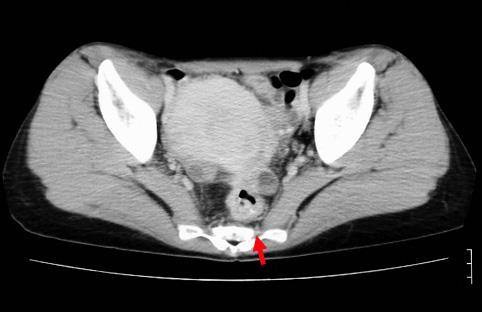

疾病(病理主体)的分类恶性上皮性肿瘤/腺癌

部位(按器官分)大肠/直肠

检查方法CT

肿瘤的肉眼分类2型(溃疡局限型)/

肿瘤最大直径40以上

肿瘤的深度s(a)